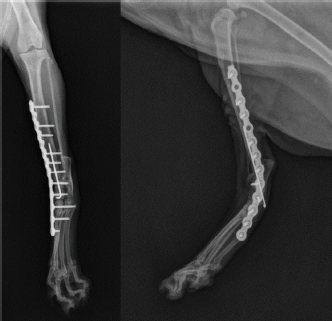

An 18-month-old female stray European cat was referred to the Veterinary Teaching Hospital of the University of Camerino, Italy. Anamnestic data reported a distal tibial epiphyseal sliding fracture (SH1) of the right hind limb inadequately treated 8 months prior with an intramedullary pin by colleagues and consequent chronic tarsocrural instability. Gait evaluation showed a non-weight bearing lameness (grade 4/5) of the right hind limb. An orthopedic examination revealed severe pain during the manipulation of the right tarsus, with bone crackling during stressed manipulation elicited by tibiotarsal joint laxity. Mediolateral and craniocaudal projections of the right tarsus showed failure of the fracture implant (intramedullary pin) caused by an inadequate choice of the apparatus and an incorrect osteosynthesis technique, with a caudomedial displacement of the right distal tibial epiphysis and a moderate process of bone remodeling and resorption (Fig. 1). The patient underwent pantarsal arthrodesis for the recovery of limb functionality. The anesthetic protocol included premedication with 3 μg/kg of dexmedetomidine (Dexdomitor 0.5 mg/ml; Orion Corporation, Finland), 0.3 mg/kg of methadone (Semfortan 10 mg/ml; Dechra, Italy), and 3 mg/kg of ketamine (Ketavet 100; Intervet Productions s.r.l., Italy) administered intramuscularly (IM). General anesthesia was induced with 4 mg/kg of propofol (Fresenius Kabi, Isola della Scala, Italy) administered intravenously (IV) and maintained with oxygen and isoflurane. When a good anesthesia plan was achieved, the femoral–sciatic nerve block was carried out with 0.2 ml/kg of lidocaine (Xylocaine 2%; Zidus Cadila, India). The affected limb and the contralateral foreleg were clipped, and a 4% chlorhexidine gluconate detergent was used for the preliminary preparation of the surgical sites, with a minimum contact time of 5 minutes. The patient was positioned in right lateral recumbency, with the affected limb toward the operating table and the contralateral limb fixed in the abduction position. Cefazolin (Cefazoline Teva; Teva s.r.l., Italy) was administered IV (22 mg/kg) approximately 30 minutes before the skin incision. Under complete aseptic precautions, the craniomedial approach was carried out to expose the tarsal joint. A skin incision, the same length as the plate, was made on the caudomedial aspect of the distal tibia and the craniomedial aspect of the tarsus and proximal metatarsus. The intramedullary pin was removed and sent to the laboratory for bacteriological examination. The tarsocrural, intertarsal, and tarsometatarsal joints were exposed, and the articular cartilage was removed with a high-speed burr. The autologous bone graft was collected from the cancellous bone of the contralateral humerus and was subsequently inserted into the joint spaces. After joint reduction, pantarsal arthrodesis was performed. A 1.2-mm Kirschner wire was driven through the calcaneus into the tibia, and a Compact UniLock 2.0 mandible locking plate (DePuy Synthes, Oberdorf, Switzerland) of 1.5-mm thickness was contoured to achieve the functional angle of tarsus extension and was positioned on the medial surface of the tarsus (Fig. 2). The plate was fixed with ten 2.0 mm locking screws and a cortical screw. The soft tissues were sutured by planes using a USP 3/0 absorbable monofilament thread. No tension at the suture lines was observed. The surgery lasted for 63 minutes. At the end of the surgery, an X-ray examination (Fig. 3) showed a good apposition of the fracture, with a slight internal rotation of the calcaneus; the apparatus seemed adequate, with a total plate screw density (PSD) of 0.85. The joint was fixed at 137° in extension. After radiographic examination, a soft padded bandage was applied for 14 days, which was renewed weekly. As needed, 0.3 mg/kg of methadone (Semfortan 10 mg/ml; Dechra, Italy) was administered IM for 24 hours postoperatively. Anti-inflammatory therapy (meloxicam 0.05 mg/kg; Metacam 40 mg/ml; Boehringer Ingelheim Vetmedica, Germany) and ranitidine (2 mg/kg; Zantadine 30 mg/ml; Ceva s.p.a., Italy) IV were administered on an inpatient basis. The first orthopedic evaluation, the first day after surgery, showed an improvement in gait (grade 2/5 of lameness on walk). The cat was discharged from the hospital after 3 days with a prescription of anti-inflammatory and analgesic therapy. The head of the cat shelter was instructed to subject the cat to cage rest for 30 days. At the first follow-up, 7 days after surgery, the soft padded bandage was renewed, and the cat showed a steady improvement in gait. Fourteen days after surgery, the soft bandage was removed; the orthopedic examination showed mild improvement in gait, although second-degree lameness and an extended tarsal and flexed stifle gait persisted because of the arthrodesis procedure. No swelling or dehiscence at the surgical site or skin tension under the plate was observed; the suture was removed, and the cat was discharged with light exercise on a larger cage recommendation for the remaining 15 days. One month after surgery, at the orthopedic evaluation, the head of the cat shelter reported a slight worsening of lameness after a sharp jump had occurred 7 days prior. The patient showed good limb function, with a slight worsening of gait during the trot, and the radiographic evaluation showed good bone activity, with 50%–66% of the joint fusion and fracture healed, although a metatarsal stress fracture was revealed (Fig. 4). Four months after surgery, radiographs revealed stable implants and an almost complete fusion of the joints (Fig. 5). The surgical wound site, 30 and 120 days after surgery, healed very well, with an efficient aesthetic result of the limb, even with a slight loss of skin elasticity, which occurs naturally after surgery. The patient never showed discomfort at the implant site, even though the plate was very superficial and palpable under the thin skin (Fig. 6). Moderate free activity with gradual introduction to freedom in the feline colony was prescribed.

Fig. 3. Craniocaudal and mediolateral postoperative radiographs after pantarsal arthrodesis showing good alignment of the tibia, tarsus, and metatarsus.